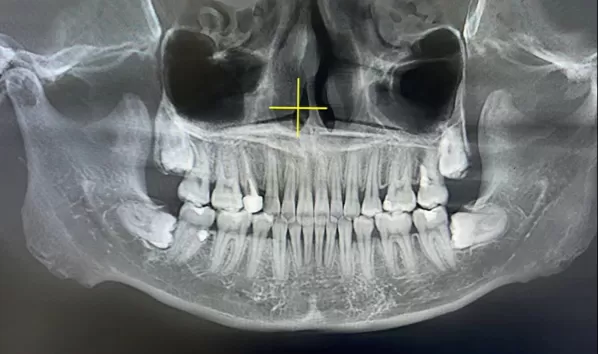

X-rays before treatment

[Panoramic Radiography/Lateral Cephalogram]